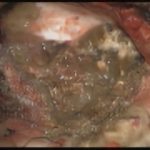

術中写真

摘出 前

摘出 中

摘出 後